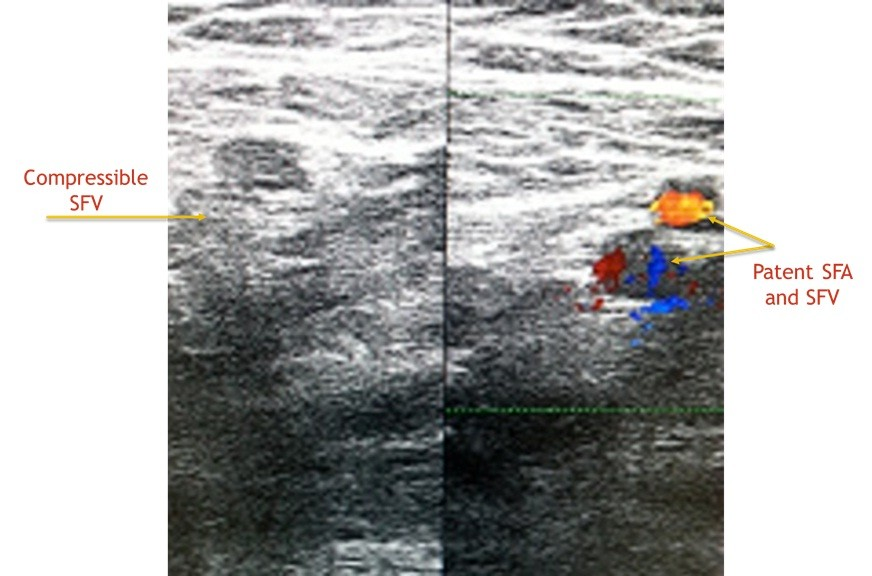

Till i spoke to him ,i thought he had a common easily curable illness.I learnt from him that ,in last 3 months he consulted 2 doctors,one of them a surgeon with no respite.One had treated him empirically and while  the other had referred him to a vascular surgeon,specialist dealing with blood vessels of legs .The vascular surgeon rightly requested a blood vessel study(Doppler ultrasound test)of the leg.I did a detailed examination of veins and arteries of the leg and found them normal.And  radiologists do not stop till they unearth the mystery of diagnosis.I gently interrogated his abdomen with ultrasound.I was not happy with what i found.It was a  dangerous tumour (sarcoma )involving muscles and deep structures of abdomen(retro peritoneum)impeding the fluid flow from leg and hence causing its swelling. Had the radiology scan been performed earlier,delay in diagnosis could have been avoided.